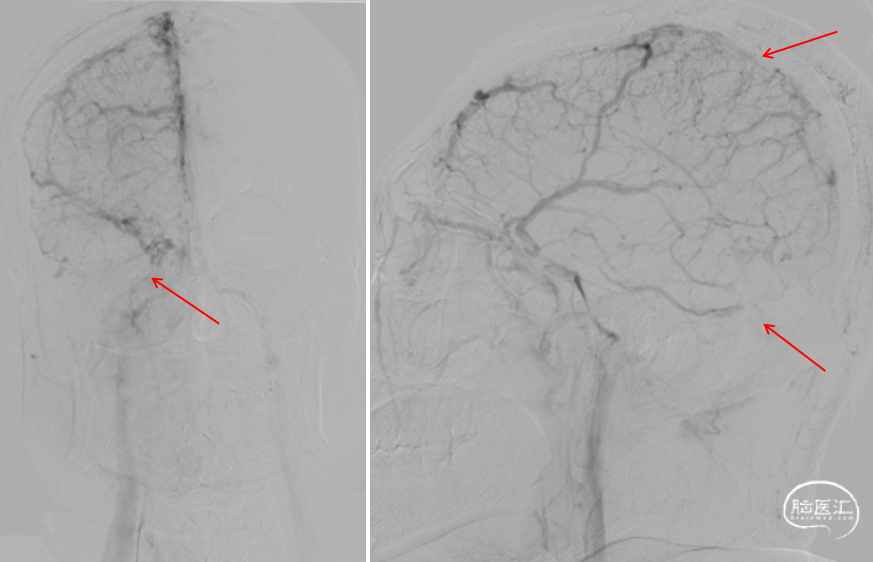

DSA(2022-1-6)

右侧颈总动脉造影示:上矢状窦显影模糊,右侧横窦、乙状窦未见显影,静脉回流缓慢。穿刺右侧颈静脉,留置8F血管鞘,全身肝素化,50万尿激酶入动脉滴注。

术前DSA